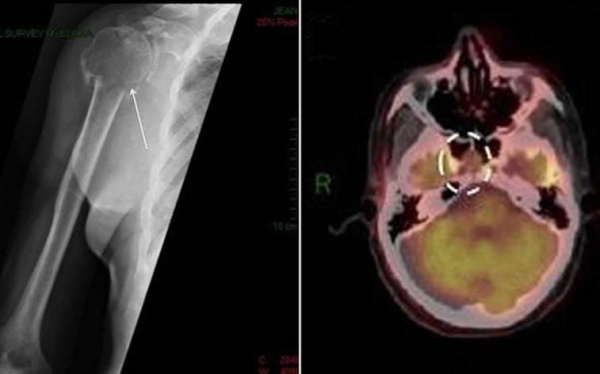

- Рентгенодиагностика. При костных болях назначается рентгенография грудной клетки, позвоночника и конечностей, с помощью которой определяются объемные новообразования. Для точной визуализации опухолей и определения степени распространенности процесса проводится КТ пораженной области тела. Методика ПЭТ-КТ показана для диагностики генерализованной плазмоцитомы.

(Слева) При аксиальной КТ в костном окне определяются почти симметричные двусторонние литические очаги затылочной кости при множественной миеломе. Из-за симметрии эти изменения могут быть менее заметны, но отмечается исчезновение наружного кортикального слоя, в норме отображающеюся в виде белой линии. Обратите внимание на эрозию кости правого канала сонной артерии.

(Справа) При МРТ Т1 в сагиттальной проекции определяются множественные низкоинтенсивные очаги множественной миеломы. Этот режим (без FS) относительно чувствителен к злокачественным процессам кости, особенно при контрастировании всею черепа и/или при записи постконтрастных снимков.